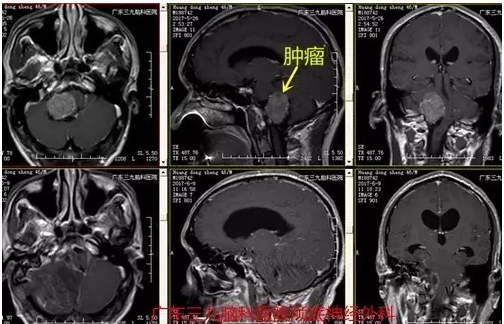

图4:术后术后磁共振提示肿瘤全切

针对脉络丛类肿瘤的治疗,目前共识为首选手术完整切除,可达治愈标准,本例病变贴近脑干及枕骨大孔区,手术切除难度较大,术中成功予病变基本切除,术后患者目前神志已清,一般情况良好。